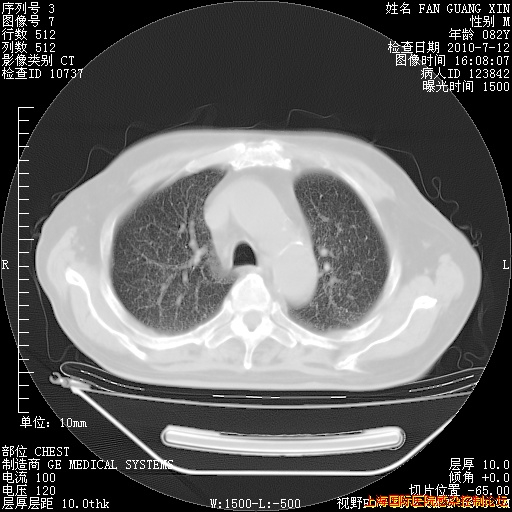

补发6月12日肺部CT肺窗

6月12日肺窗

整整相隔30天的肺部CT好像有所好转啊。甲强龙减量第3天,需要观察体温。